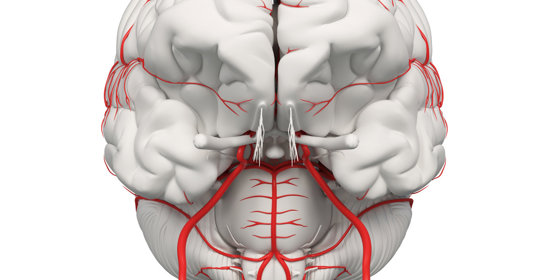

大腦與神經

橋腦出血:中風復健方法與時間

橋腦出血:處理與預防措施

橋腦出血:治療措施與緊急性

橋腦出血:差異與治療